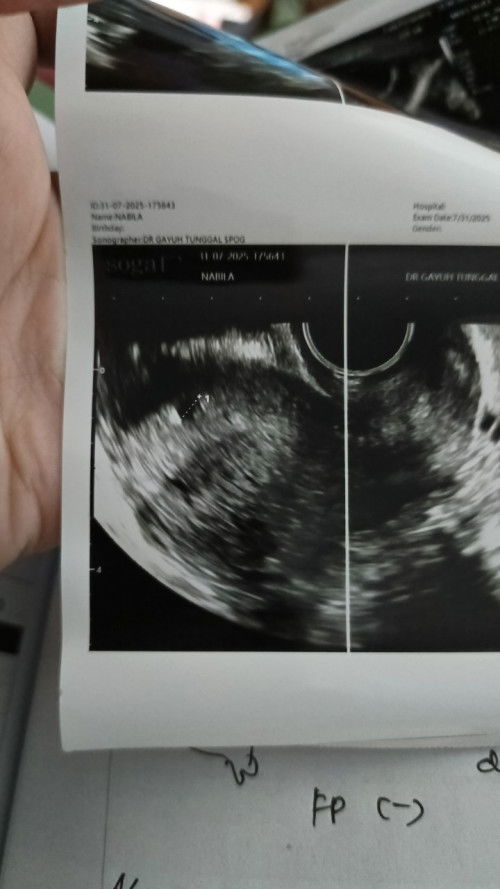

Apakah GS ukuran 0,68 normal?

Berapa minggu ya kira2, haid terakhir tgl 13 Juni 2025

dokter bilang nanti suruh kontrol lagi bulan depan, saya sedikit khawatir tp saya berharap penuh janin saya akan baik2bsaja bun